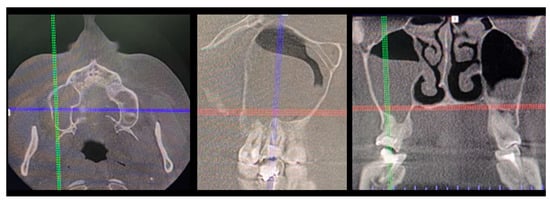

Figure 1. A case after the removal of the first upper right molar and curettage of some periapical inflamed tissue resulting in the loss of buccal cortical plate and opening of a huge oro-antral communication (CBCT scans in sagittal view).